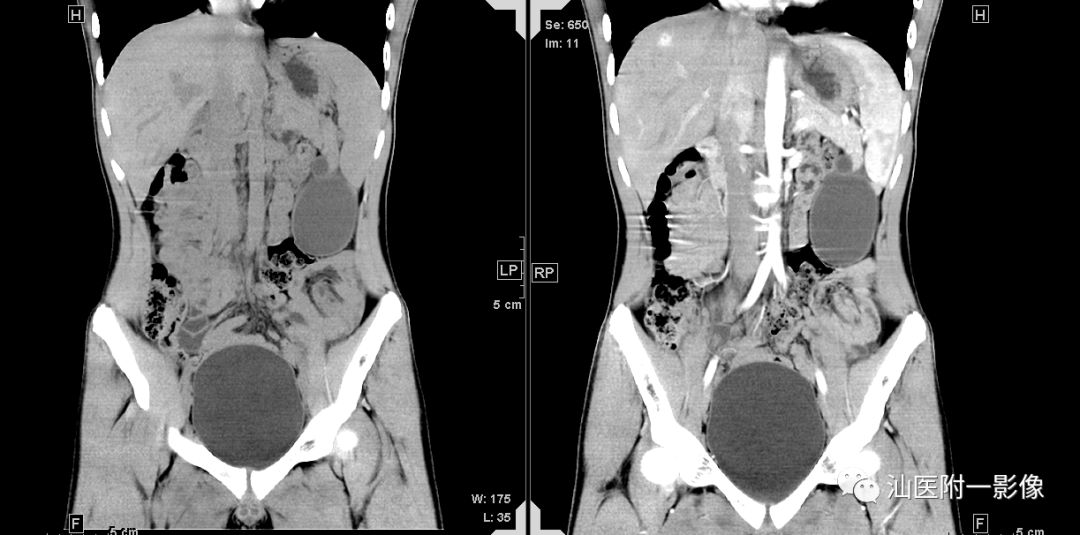

病例一 胰腺先天性囊肿